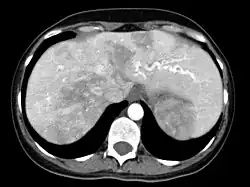

Leber

Auch in der Leber können Gefäßkurzschlüsse (Shunts) auftreten. Diese können zu einer Überlastung des Herzens führen, was von den Betroffenen häufig als Abgeschlagenheit und mangelnde körperliche Belastbarkeit, ähnlich wie bei der Blutarmut, empfunden wird. Die medikamentöse Verbesserung der Herzfunktion wird häufig als erster Schritt der Behandlung versucht. Es gibt eine Reihe eingreifender Behandlungen, insbesondere die Embolisation (s. o.) und die Lebertransplantation. Da die Nebenwirkungen gravierend sein können, ist hier ähnlich wie bei den CVM ein sorgfältiges Abwägen der Vor- und Nachteile erforderlich.